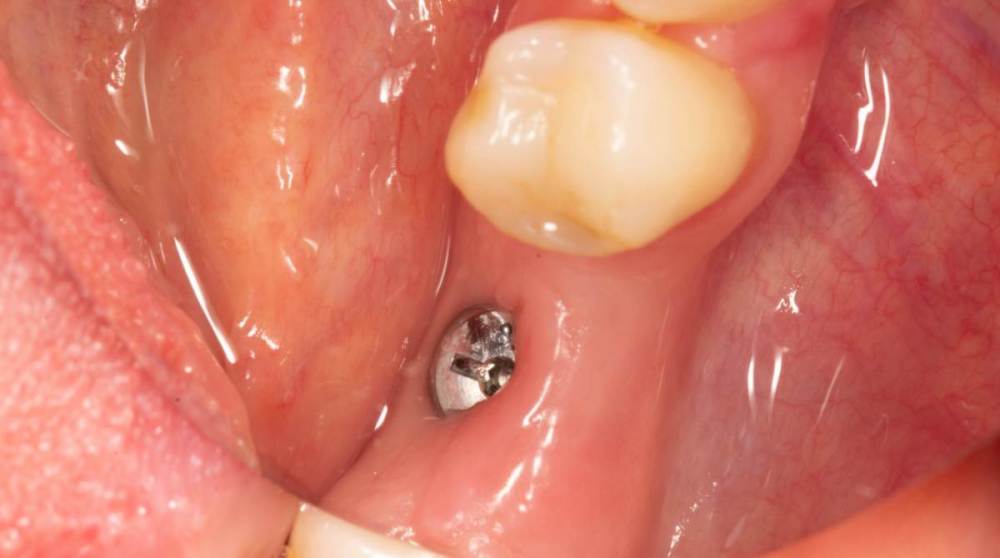

Женька Опубликовано 19 июня, 2023 Поделиться Опубликовано 19 июня, 2023 Здравствуйте, коллеги. Примерно с нового года начал ставить ТЛ имплантаты Дентиум. Что-то под заглушку (не поймал торки, представляете?). Что-то на низких формирвателях. И вот пришла пора протезирования, но отпустить к ортопеду не подготовив десну - не получается. Создал сам себе проблем, сегодня вот исправлял. Получилось неплохо? 3 Ссылка на комментарий

TIGER Опубликовано 20 июня, 2023 Поделиться Опубликовано 20 июня, 2023 Это ж не TL,cубкрестально же.А так я бы длиннее брал ССТ,с захватом соседей Ссылка на комментарий

Женька Опубликовано 20 июня, 2023 Автор Поделиться Опубликовано 20 июня, 2023 @TIGER в смысле это не ТЛ?))) Фото с редукцией не сделал. А то что, шейку погружал - так нужно было. Но это ТЛ. Поверьте) я был на имплантации) Ссылка на комментарий

АнтонТЛТ Опубликовано 20 июня, 2023 Поделиться Опубликовано 20 июня, 2023 Думаю имеется ввиду что имплантат TL установлен по протоколу BL Ссылка на комментарий

Женька Опубликовано 20 июня, 2023 Автор Поделиться Опубликовано 20 июня, 2023 @АнтонТЛТ мы же позиционируем платформу относительно зенита? Есть ли разница тогда, какой имплантат мы выбираем? Вообще весь смысл здесь был заложен в том, что толщина гребня была не очень. Хотелось поставить тонкий имплантат 3.6. Но рисковать тонкой платформой не хотелось, поэтому выбор пал на 4.8 платформу ТЛ и тело имплантата 3.6 1 Ссылка на комментарий

АнтонТЛТ Опубликовано 20 июня, 2023 Поделиться Опубликовано 20 июня, 2023 Конечно относительно зенита, не вдаваясь в подробности, для BL глубже зенита на 3мм, для TL вровень с зенитом. Ссылка на комментарий